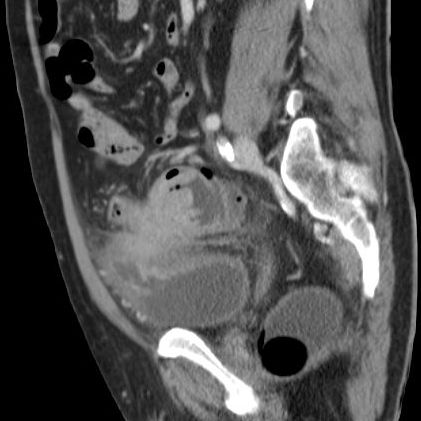

| Ileus | 78-jährige Frau in der Notaufnahme wegen Ileus. Tumor am deszendo-sigmoidalen Übergang. Hemokolektomie: Ulzeriertes Adenokarzinom pT3b pN1a (1/12)Mo L1 Vo. | ||

![]() |

![]() | |

| Ileus | Das CT zeigt einen stenosierenden Sigmatumor mit ausgeprägtem Ileus. |